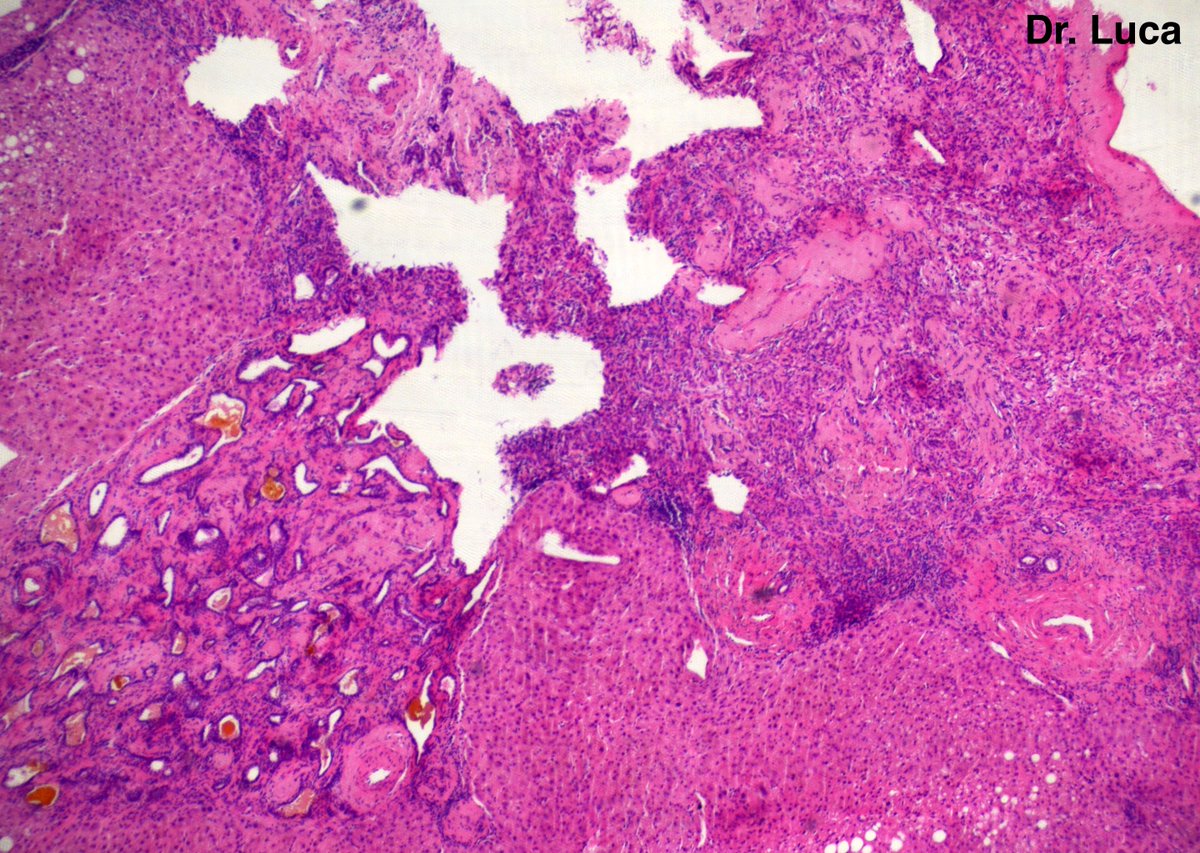

Kidney Monster! 3kg mass, 1% white solid areas, your Dx before H&E? @AkgulMd @Pathmath1 @goziemnweke @Teclis82 @MichelleDunno17 @PoloniaAntonio @kis_lorand @crazylymphocite @kriyer68 @D4L14H @ritaescarvalho @JPintoPath @Andres_Matoso @rajalbshah @Pathology36 #gupath #PathTwitter

10

19

48